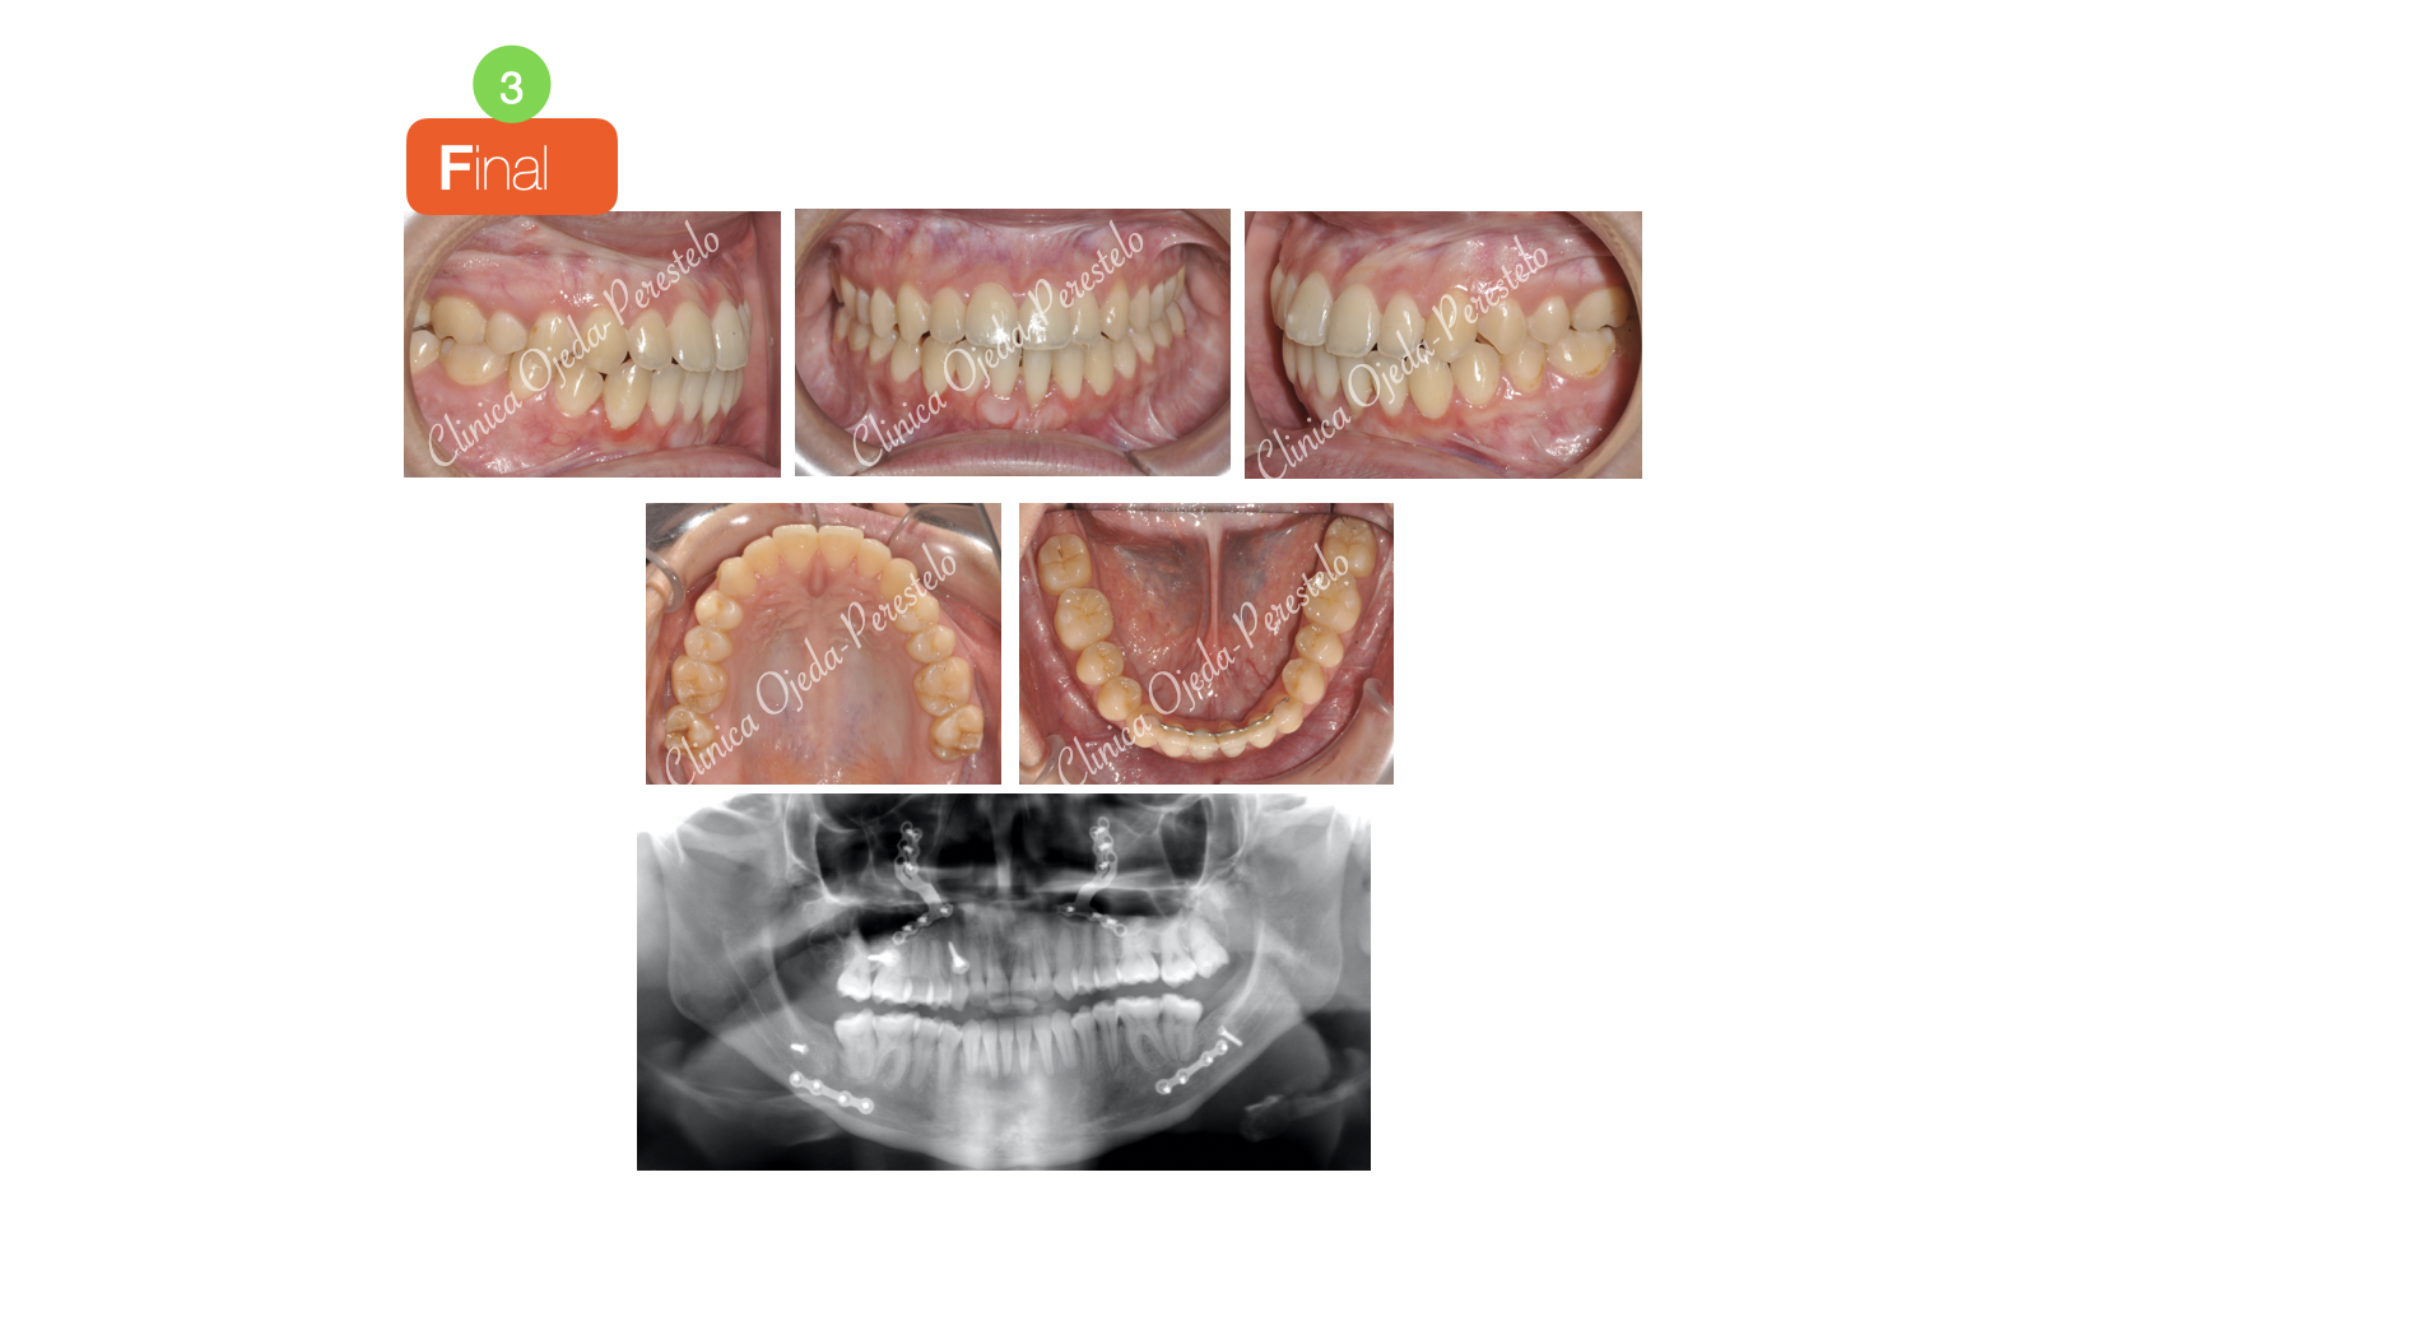

Clase III ósea severa con C.Ortognática

Paciente que consulta por clase III ósea severa y mordida cruzada e invertida. Presenta limitaciones severas para realizar una correcta función masticatoria.

La paciente quiere cambios faciales y decidimos realizar una primera fase de Ortodoncia prequirúrgica consistente en centrar los incisivos superiores e inferiores sobre su base ósea con brackets (Sistema Damon).

La intervención quirúrgica ha sido realizada por el equipo del Dr Hdez-Alfaro y se planificó con Lefort y Avance del Maxilar conjuntamente con Osteotomia Sagital de Rama para centrado y retrusión Mandibular. Quisiéramos destacar la mejora en el perfil, su sonrisa y en su función masticatoria tras finalizar el tratamiento.